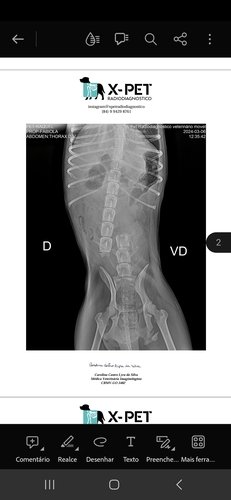

Sou Gladerson e fiz essa vakinha para ajudar o Sr. Francisco Tércio, ele precisa de ajuda para cuidar da cadelinha que ele resgatou. Presenciamos o atropelamento da cachorrinha na BR 101, o motorista se evadiu, motociclistas tiralam ela da via, a PRF não foi ajudar, os Bombeiros também não, e apenas disseram que levássemos ela aos Zoonoses da cidade para a eutanásia. Como a cadelinha sobreviveu, o senhor Tércio se dispôs a cuidar dela, mas uma cirurgia é necessária para colocar a coluna dela no lugar. Duas ONG's têm nos ajudado, com exames, remédios e informações, mas não temos recursos para pagar a cirurgia que ela precisa.